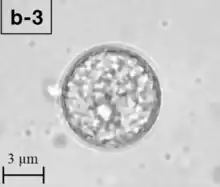

| A Balamuthia mandrillaris cyst | |

Balamuthia's lifecycle, like the Acanthamoeba, consists of a cystic stage and a non-flagellated trophozoite stage, both of which are infectious, and both of which can be identified in the brain tissue on microscopic examination of brain biopsies performed on infected individuals. The trophozoite is pleomorphic and uninucleated, but binucleated forms are occasionally seen. Cysts are also uninucleated, possessing three walls: an outer thin irregular ectocyst, an inner thick endocyst, and a middle amorphous fibrillar mesocyst.[9]

Biopsies of skin lesions, sinuses, lungs, and the brain can detect of B. mandrillaris infection. The amoeba cannot be cultured on an agar plate coated with E. coli because, unlike Naegleria or Acanthamoeba, Balamuthia mandrillaris does not feed on bacteria. Instead, Balamuthia must be cultured on primate hepatocytes or human brain microvascular endothelial cells.[14] Formalin-fixed paraffinized biopsy specimens may indicate Balamuthia trophozoites in the perivascular space. The cysts can be visualized by calcofluor white, which binds to glycans on the cyst wall. Trophozoites appear circular during infection.[13]